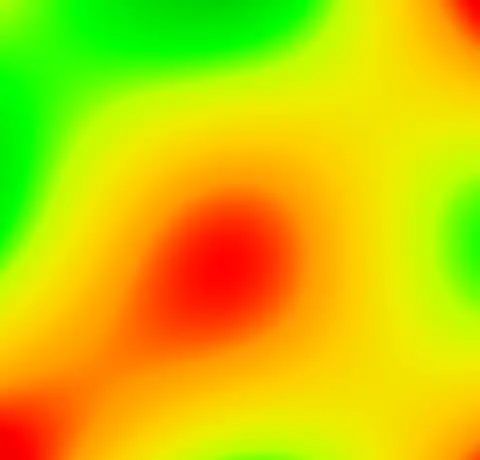

And then produce an image of it using the Spectral colormap

mincpik -scale 2 field.mnc -slice 150 -lookup -spectral field.png

And then for completeness sake, here are the original and corrected image using a spectral colormap to better visualise the change. Note that in the second (corrected) image the intensity of the white matter is more uniform (the red part).